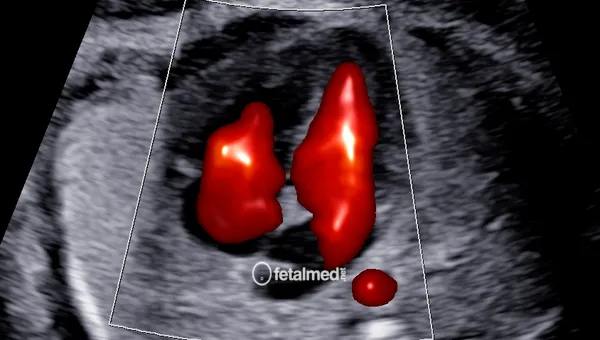

Ecocardiografia Fetal

Ecocardiografia fetal com Doppler colorido para avaliação detalhada do coração do bebê. Diagnóstico de cardiopatias congênitas em Curitiba.